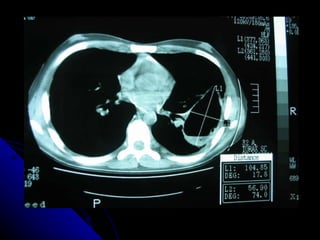

SÍNDROME PARENQUIMAL Conjunto de signos radiográficos que traducen una lesión en el parénquima pulmonar, la  que  puede ser localizada o difusa. Didácticamente podemos dividirlo en tres tipos: Alveolar Intersticial Mixto ( alveolo intersticial)

SÍNDROME PARENQUIMAL Conjuntode signos radiográficos que traducen una lesión en el parénquima pulmonar, la que puede ser localizada o difusa. Didácticamente podemos dividirlo en tres tipos: Alveolar Intersticial Mixto ( alveolo intersticial)